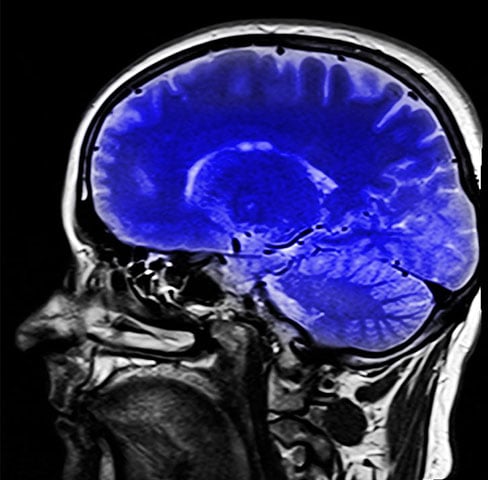

Desconhecido, nutriente é vital para o bom desenvolvimento do cérebro